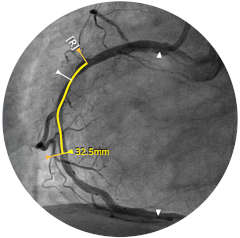

Einführung der völlig neue Anwendungsplattform IntraSight von Philips – Zusammenspiel von Bildverarbeitung, Physiologie, Koregistrierung und Software für eine optimale Patientenversorgung. IntraSight bietet eine umfassende Palette klinisch bewährter Modalitäten wie iFR/FFR, IVUS und Koregistrierung* für einfachere komplexe Interventionen, schnellere Routineverfahren und eine verbesserte Patientenversorgung.

IntraSight ist auf Basis einer intelligenten, anwendungsbasierten Plattform konzipiert, die sich bei neuen verfügbaren Anwendungen und Modalitäten an die sich ändernden Anforderungen Ihres Labors anpassen lässt – und das ohne neue Hardware erwerben zu müssen. Nur IntraSight von Philips bietet Ihnen erstklassige Bildverarbeitungs- und Physiologie-Tools mit iFR, iFR-Koregistrierung*, FFR, IVUS, IVUS-Koregistrierung* und Angio+*. Dank seiner modularen Architektur bleibt IntraSight über die neuesten Entwicklungen und wichtigen Sicherheitsupdates auf dem Laufenden.

Abbildung 1